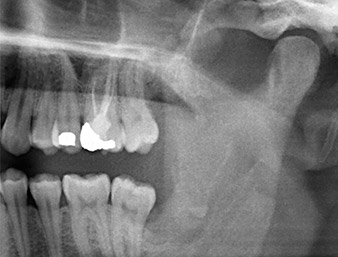

Il residuo di radice nella regione del dente 38 (LL8) mostrava già stretta vicinanza al nervo alveolare inferiore nell'ortopantomografia. La radice si era spezzata durante l'osteotomia ma non era stata rimossa dal dentista che aveva eseguito l'operazione a causa di dolore intraoperatorio. Per garantire il minor trauma possibile al tessuto, la nuova osteotomia doveva essere eseguita utilizzando un sistema piezochirurgico. Il paziente presentava un'anamnesi non rilevante e non era fumatore.

Nell'immagine 3D (tomografia volumetrica digitale) era visibile che il residuo di radice era collocato in posizione distocaudale nella transizione dalla porzione orizzontale alla porzione ascendente della mandibola (Fig. 2).

In base all'anamnesi, il paziente (non fumatore, 26 anni) presentava probabilità molto elevate di un outcome positivo. A causa dell'indicazione della stretta vicinanza del residuo di radice al nervo alveolare inferiore nella radiografia panoramica, è stata utilizzata anche la tomografia volumetrica digitale (6).